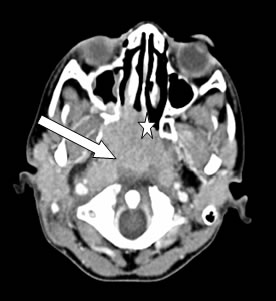

Computed tomography (CT) scan of neck showed large aggressive soft tissue mass in the nasopharynx with infiltration of prevertebral muscles as well erosion of pterygoid muscles with extension into right pterygopalatine fossa, ethmoid and sphenoid sinuses (Figure 2). There were multiple enlarged lymph nodes on both sides of upper neck. Chest radiograph was clear and ultrasound abdomen was normal.

Figure 2: Axial CT scan showed mass at nasopharyngeal region (arrow) with local infiltration to the right posterior inferior turbinate and nasal septum (star)